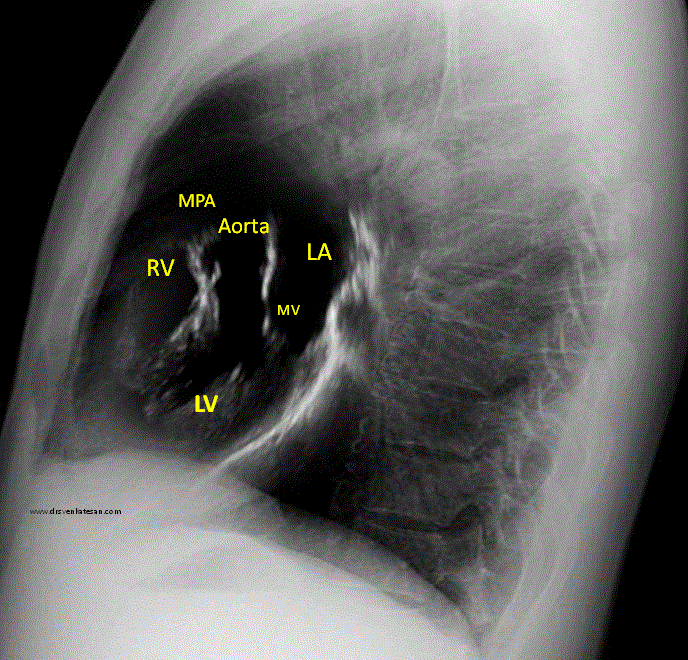

X ray chest left lateral view is fused with para- sternal long axis view. Please note this is not true anatomical correlates. The RV shown in echo is actually RVOT but in X-ray its more of RV body .

* A note of caution : The fused Images are rough attempt to co-register x-ray with echo. There is sophisticated software in some new generation cath labs to mix fluro images with live TEE data that aid in Interventions.